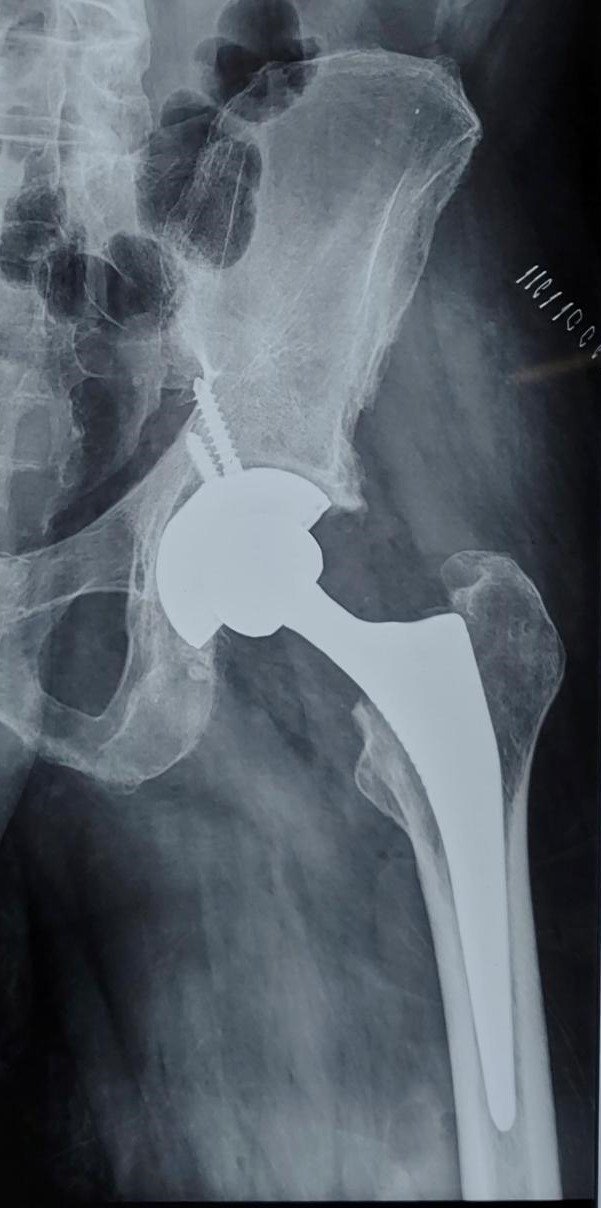

Ankylosing Spondyltis of Hip

Post-Op X-Ray